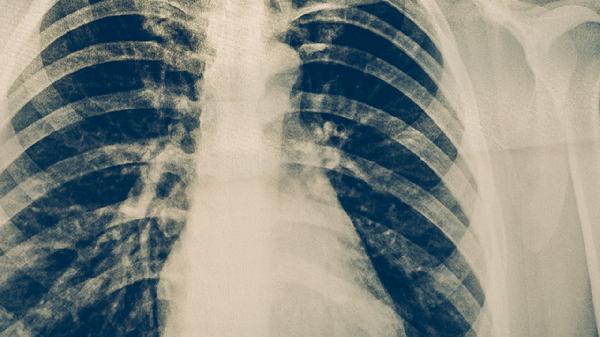

肺结核患者用药期间应保持高蛋白饮食如鸡蛋、鱼肉,避免酒精及肝毒性食物。适当进行散步等低强度运动增强体质,但需避免过度消耗体力。所有药物调整必须由专科医生根据检查结果决定,不可自行增减剂量或停药。治疗全程需配合痰检及影像学复查,确保疗效与安全性平衡。